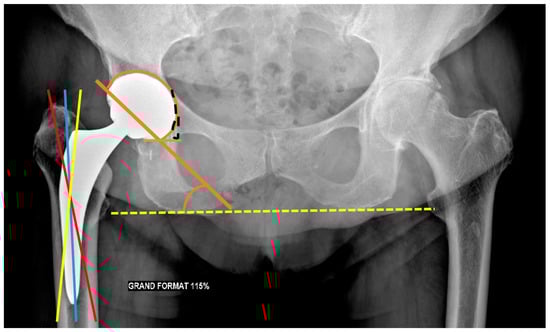

| Measurement | Normal Value | Consequences of Mispositioning |

|---|---|---|

| Leg Length | < 0.5–1 cm of differences between both sides | Increased discrepancy: gluteal and iliopsoas muscles affection |

| Acetabular side | ||

| Frontal acetabular inclination | 40 ± 15° | - Decreased: hip abduction limitation |

| - Increased: dislocation risk | ||

| Sagittal acetabular inclination | 35–40 ± 10° in standing position | - Increased: posterior impingement, anterior dislocation |

| 52 ± 11° in sitting position | - Decreased: anterior impingement between the cup and the neck, posterior dislocation | |

| Acetabular anteversion | 5–25° | - Lack of anteversion or retroversion: posterior dislocation, iliopsoas impingement |

| - Excessive anteversion: anterior dislocation | ||

| Acetabular center of rotation position | Similar to the contralateral hip | Lateralized: dislocation risk |

| Femoral Offset | 41–44 mm (or similar to contralateral hip) | - Decreased: limping, mobility limitation, and dislocation by gluteal muscles weakness |

| - Increased: gluteal muscles pain and polyethylene wear | ||

| Femoral side | ||

| Femoral Stem position | Neutral or slight valgus | Periprosthetic fracture and stress reaction in case of varus |

| Femoral Neck Anteversion | 10–15° | - Increased: anterior dislocation and ischio-femoral impingement |

| - Decreased: posterior dislocation | ||

| Femoral Head | Centered or slightly inferiorly located | - Particle disease if located upwards (wear) |